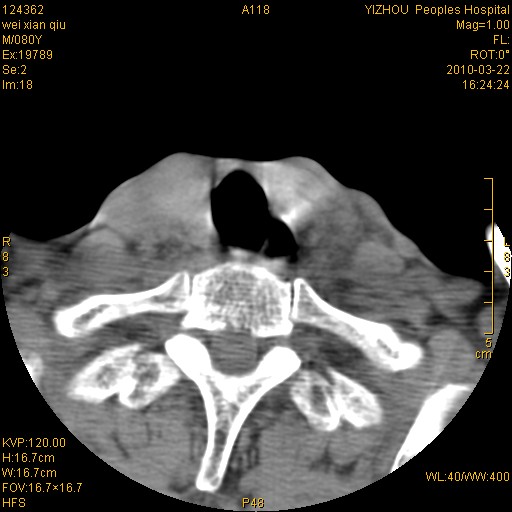

男,80岁.声嘶三月余.

右侧喉癌可能性大,建议喉镜检查

喉前庭右侧壁明显增厚,并见向内突出的软组织密度新生物,表面光滑,其后方软组织层次尚清晰,多考虑:喉部乳头状瘤!建议喉镜并病检!

右侧声们下区新生物